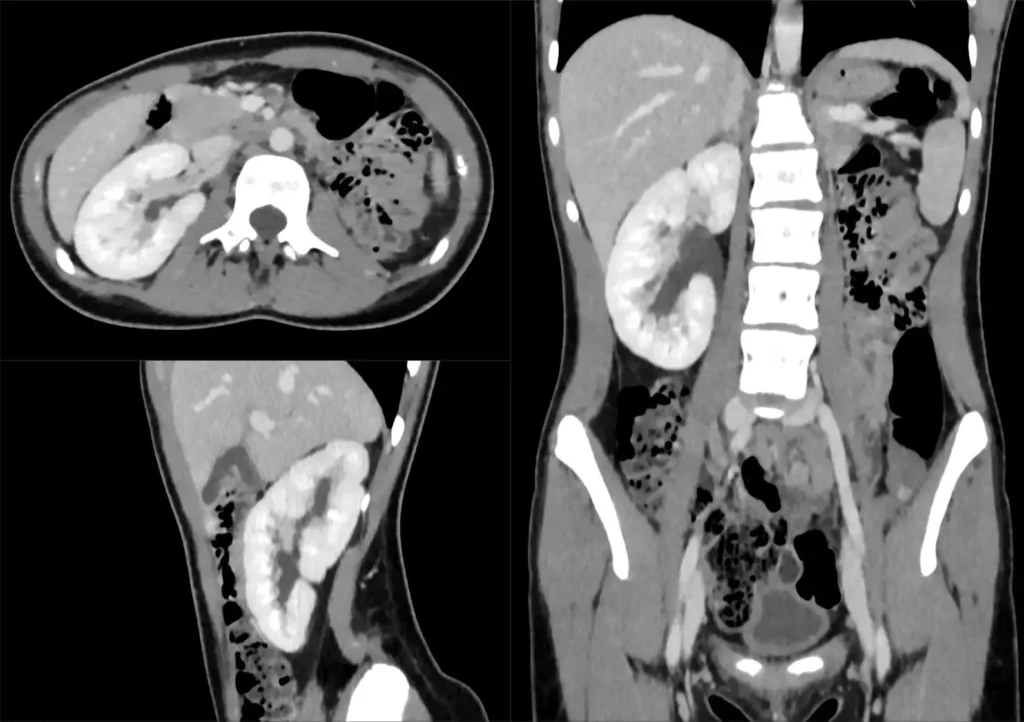

Eine Nierenagenesie kann während der Schwangerschaft oder nach der Geburt diagnostiziert werden. Die Diagnose erfolgt in der Regel durch folgende Methoden:

- Pränataler Ultraschall: Ein Ultraschall während der Schwangerschaft kann die fehlende Niere erkennen.

- Bildgebende Verfahren: Bildgebende Verfahren wie Röntgen, CT oder MRT können verwendet werden, um die Struktur der Nieren zu untersuchen.